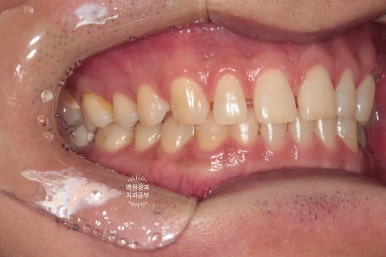

정면에서는 보이지 않지만, 측면에서 보았을 때 가장 끝에 제작된 임플란트가 보입니다.